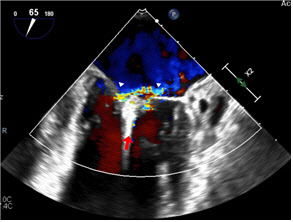

인천세종병원에 따르면 승모판막 부전 환자를 대상으로 허벅지 정맥에 미세도관(카테터)을 넣어 심장까지 접근해 승모판막의 전엽과 후엽을 클립으로 고정하는 마이트라클립 시술을 시행하고 있다. 카테터 끝에 장착된 클립 장치를 이용해 느슨하거나 제대로 닫히지 않는 승모판을 고정하면서 혈액 역류를 차단하는 방식이다. 모든 시술 과정은 심장초음파 및 X-ray 영상 장비로 실시간 관찰하며 진행된다.